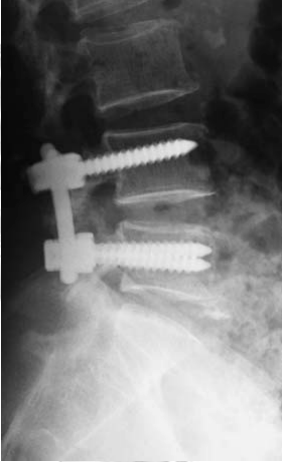

Has imaging studies showed grade 1 degenerative spondylolisthesis L45 with moderately severe subarticular and subarticular stenosis at L5S1 and L34.

Decompression of L34, L45 and L5S1 were done. L45 through a partial laminectomy of L4 and L34, L5S1 through limited interlaminar approach. L45 was stabilsed with rigid fixation and fusion using pedicle screws, L34 with a dynamic interspinous devices and L5S1 was decompressed only.

This patient illustrates one of many patterns in patients presenting with lumbar spinal canal stenosis and the available options in surgical treatment. Decompression is necessary to relieve nerve compression. Additional procedures often aim to treat back pain or prevent further deterioration and recurrence of symptoms. The commoner options include fusion and soft stabilization. To treat back pain and to prevent deterioration of the spondylolisthesis, L45 fusion was done. At L34, an interspinous device using silicone-based implant allows assisted motion and helps to maintain an open foraminal canal. At L5S1, the small sacral spinous process makes the interspinous device interspinous device ineffective and as fusion was not yet needed, only a decompression was done. DIAM (Medtronics)